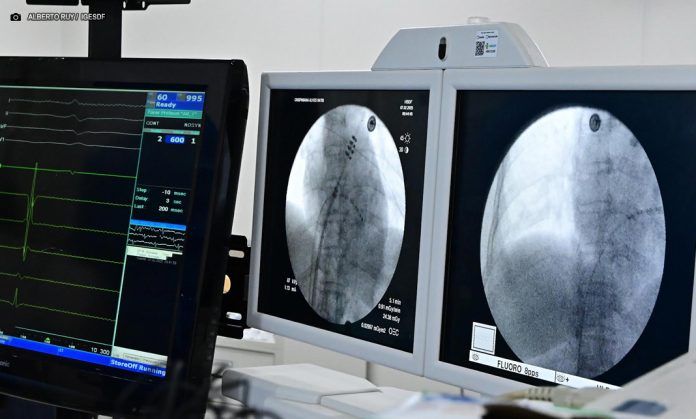

HBDF realiza tratamento de arritmias cardíacas com a ablação e aplicação de pulso de elétrons – Foto: Alberto Ruy/ IgesDF

A eletrofisiologista invasiva Carla Septimio Margalho, supervisora do Programa de Residência em Eletrofisiologia Clínica e Invasiva do Hospital de Base, explica que a técnica é revolucionária. “A PFA utiliza uma tecnologia nova, desenvolvida recentemente, que permite a realização da ablação com mais segurança e eficiência. O procedimento, chamado ablação de fibrilação atrial com aplicação de pulso de elétrons, é um marco no tratamento da arritmia e já tem mostrado resultados promissores”, destaca.

“O que antes levava 8 a 10 horas e exigia UTI, agora pode ser realizado em cerca de 55 minutos. O paciente pode ser encaminhado à enfermaria e recebe alta em poucos dias, o que reduz riscos, otimiza o atendimento e diminui custos”, explica o cardiologista Henrique Cesar.